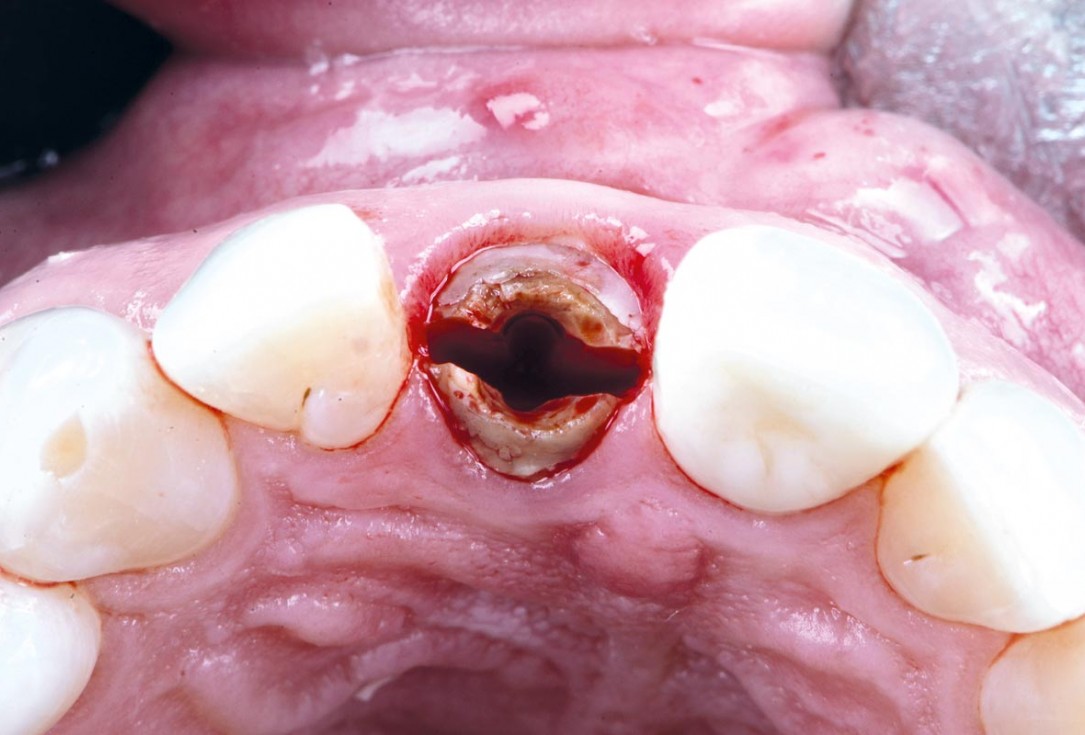

06/30 - Atraumatic extractionExcellent aesthetic result of buccal augmentation with mucoderm® and maxgraft® after immediate implant placement - 3-years follow-up - Dr. A. Puišys

07/30 - Atraumatic extractionExcellent aesthetic result of buccal augmentation with mucoderm® and maxgraft® after immediate implant placement - 3-years follow-up - Dr. A. Puišys

08/30 - Atraumatic extractionExcellent aesthetic result of buccal augmentation with mucoderm® and maxgraft® after immediate implant placement - 3-years follow-up - Dr. A. Puišys